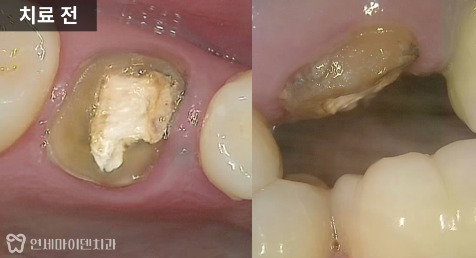

임시 재료를 제거하고 내부를 확인해 보니

거타퍼차(GP)라는 신경치료

마무리 재료가 채워져 있었습니다.

레진코어와 기둥 보강이 중요한 이유

신경관 내부는

다시 깨끗하게 정리

거타퍼차는 신경관

내부에서만 마무리

상부는 치아와 접착되는

레진코어로 단단히 수복

또한 치아가 많이 남아 있지 않은 경우에는

기둥 보강을 함께 진행하면

수복물의 탈락을 막을 수 있습니다.